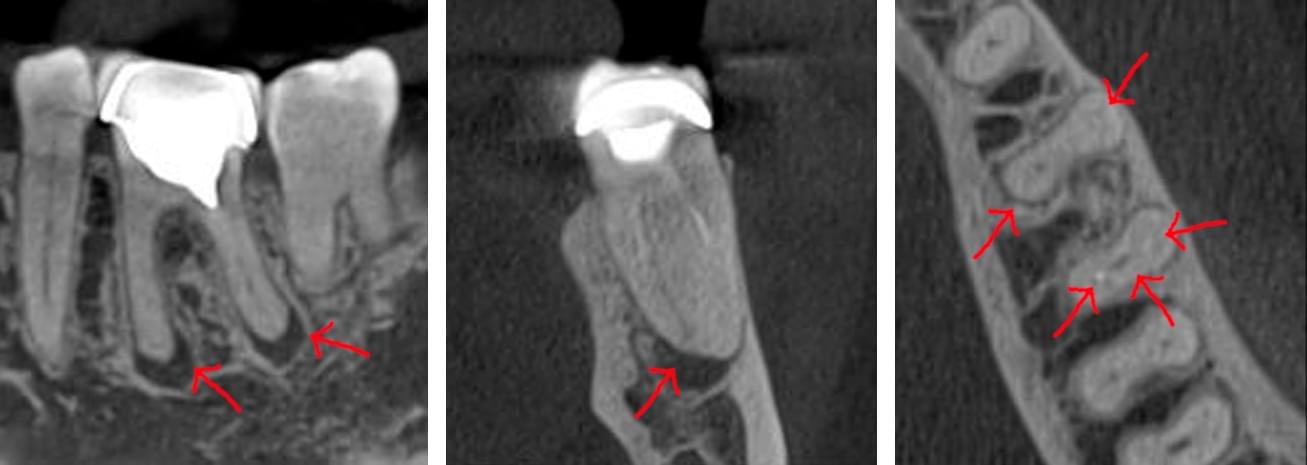

Зуб — це не просто монолітний об'єкт, а складна система мікроканалів. На плоскому 2D-знімку вони часто перекривають один одного, створюючи ілюзію простої анатомії.

Непомічений канал — це джерело майбутньої інфекції та причина «загадкового» болю після лікування. Завдяки високій роздільній здатності обладнання MyRay, лікар бачить кожен мікронний канал ще до того, як візьме до рук інструмент.

Коли коріння «ховає сюрпризи» - Корені зубів часто мають складну кривизну, гачкоподібні закручення або розгалуження, які на звичайному 2D-знімку накладаються один на одного, створюючи ілюзію прямого каналу. На плоскій картинці неможливо побачити реальний об'єм та напрямок вигину, що критично важливо при видаленні «зубів мудрості» або ендодонтичному лікуванні. КТ MyRay дає змогу лікарю заздалегідь побачити 3D-геометрію кожного кореня, оцінити його близькість до нижньощелепного нерва чи гайморової пазухи та підібрати правильну тактику роботи. Це мінімізує ризики поломки інструменту в каналі або травмування сусідніх структур, перетворюючи складну хірургію на прогнозовану процедуру.